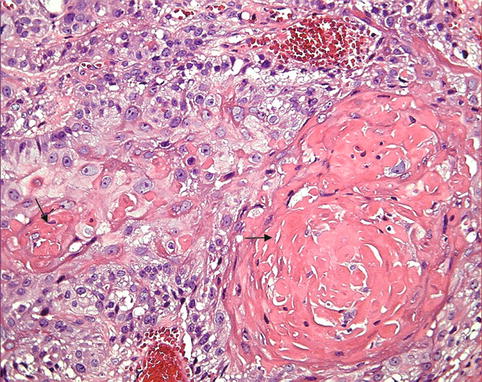

Фотографии и изображения, связанные с симптомами первичного склерозирующего холангита